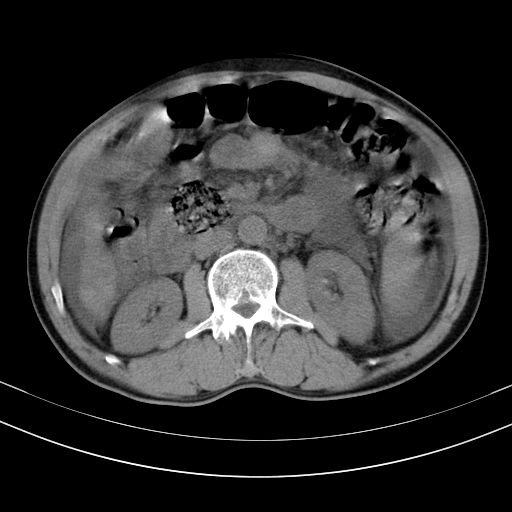

以下是引用随光逐影在2010-2-28 10:23:00的发言:[br]1)考虑肝癌;建议行ct增强扫描检查。2)肝硬化,脾大,腹水。3)慢性胆囊炎。

以下是引用dyqct在2010-2-28 16:44:00的发言:[br][quote]以下是引用随光逐影在2010-2-28 10:23:00的发言:[br]1)考虑肝癌;建议行ct增强扫描检查。2)肝硬化,脾大,腹水。3)慢性胆囊炎。